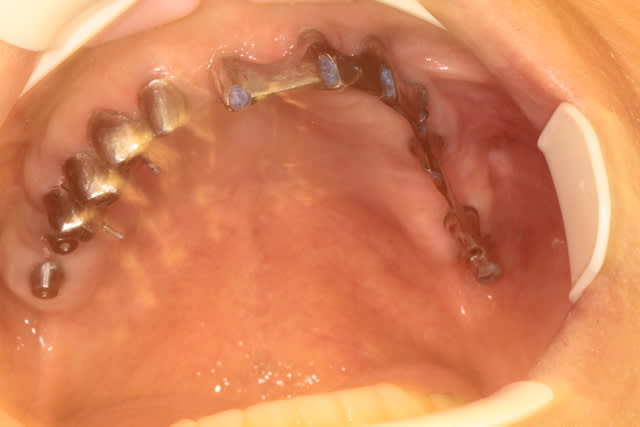

et là !

Image8 qjk3fn - Eugenol

pxav

30/04/2010 à 14h37

si le sujet c'est l'implant c'est correct, si c'est le guide c'est flou...

par contre bravo pas de sang sur les gants